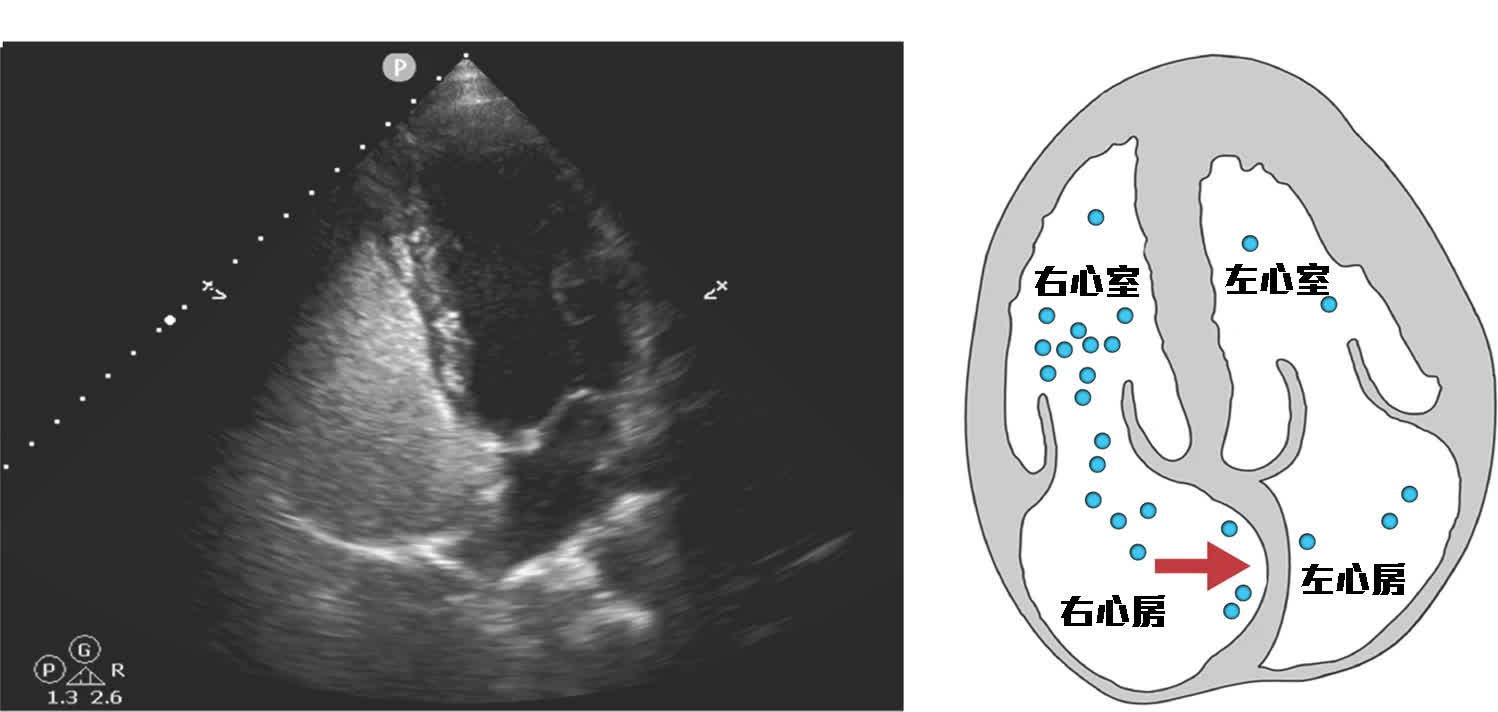

那麼怎樣知道有沒有這個結構存在呢?醫生一般可安排做心臟超聲波和鹽水氣泡測試(agitated saline test)或經頭顱血管彩超,初步看有沒有卵圓孔未閉的機會。原理是打鹽水氣泡進入靜脈血管,一般會使右邊的心臟變白(因為是有氣鹽水的關係),左邊心臟是不會變白 (因為有着牆壁隔開)。但如果病人有卵圓孔未閉,打鹽水和做特別呼吸動作時,有機會鹽水從右心房到左心房令左邊心臟亦變白。如基本檢查懷疑有卵圓孔未閉,一般醫生會建議安排做經食道心臟超聲波作進一步確實。 如經檢查後,中風患者確實有這一個結構,而其他檢查亦找不到有相關明顯中風的原因 (cryptogenic stroke)時,那麼醫生一般會建議考慮封堵這卵圓孔未閉。經多年研究顯示,如中風患者有着這個結構,但沒有其他明顯中風原因,封閉卵圓孔未閉有預防再一次中風的作用。封堵卵圓孔未閉的手術,一般比較會採用微創經導管的方法。如同有冠心病的患者做通波仔手術一樣,經大腿內側靜脈血管,透過導管將一個封堵器放在卵圓孔未閉,把這結構封堵。一般局部麻醉下亦可完成手術。需要的時間大約半小時至一個小時左右。完成手術後的朋友,需要最少服用雙抗血小版藥物三至六個月。